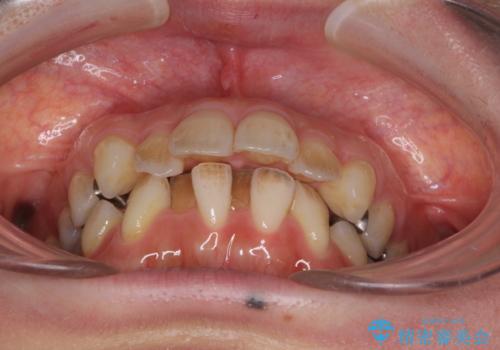

閉じにくい口元 前歯を引っ込める抜歯矯正

- 上下の出っ歯を気にして来院された患者様です。

口元を積極的に引っ込めるために、上下左右の第一小臼歯を4本抜歯することとしました。

元々ディープバイトのため、スペースを閉じている期間に上下前歯が接触してしまい、治療期間が想定よりも伸びてしまいました。